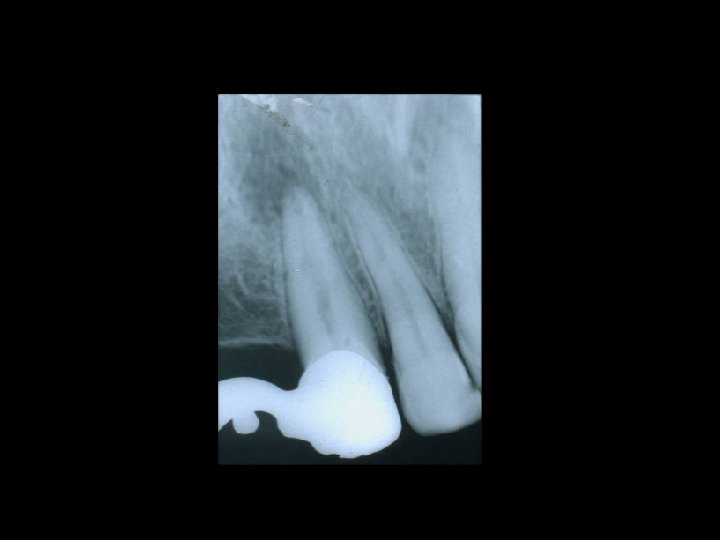

Il contenzioso PRINCIPALI AMBITI Ø Ø Ø La diagnosi La chirurgia orale La terapia conservativa Il trattamento delle anomalie dento-scheletriche La riabilitazione protesica

Responsabilità Garanzia di mezzi Ø Garanzia di risultato Ø Scelta del tipo di trattamento Ø Ø Condizioni denti Ø Condizioni delle mucose Ø Condizioni delle ATM Ø Preparazione dei denti pilastro Ø Prospettive di risultato estetico Ø Prospettive di risultato nel tempo Ø Caratteri del manufatto